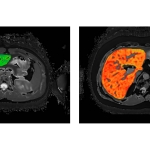

LiverMultiScan is the most comprehensive liver MR exam that measures liver fat, iron, fibrosis, and inflammation. The technology was developed by Perspectum, leaders in innovative imaging solutions for patients with metabolic disease. LiverMultiScan is designed to help clinicians care for patients with fatty liver disease such as non-alcoholic steatohepatitis (NASH). These patients typically undergo blood tests then an invasive biopsy procedure. LiverMultiScan reduces the need for liver biopsy and provides the care team with a quantitative report to help monitor therapy.